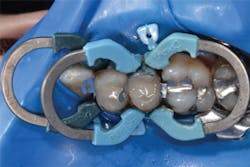

Figure 12: Final preparations on teeth Nos. 4 and 5. The Palodent Plus Sectional Matrix System has been used to isolate the MOD prep on tooth No. 4 and MO prep on tooth No. 5. The Palodent Plus Sectional Matrix System can be configured to restore multiple surfaces and multiple teeth in the same quadrant.